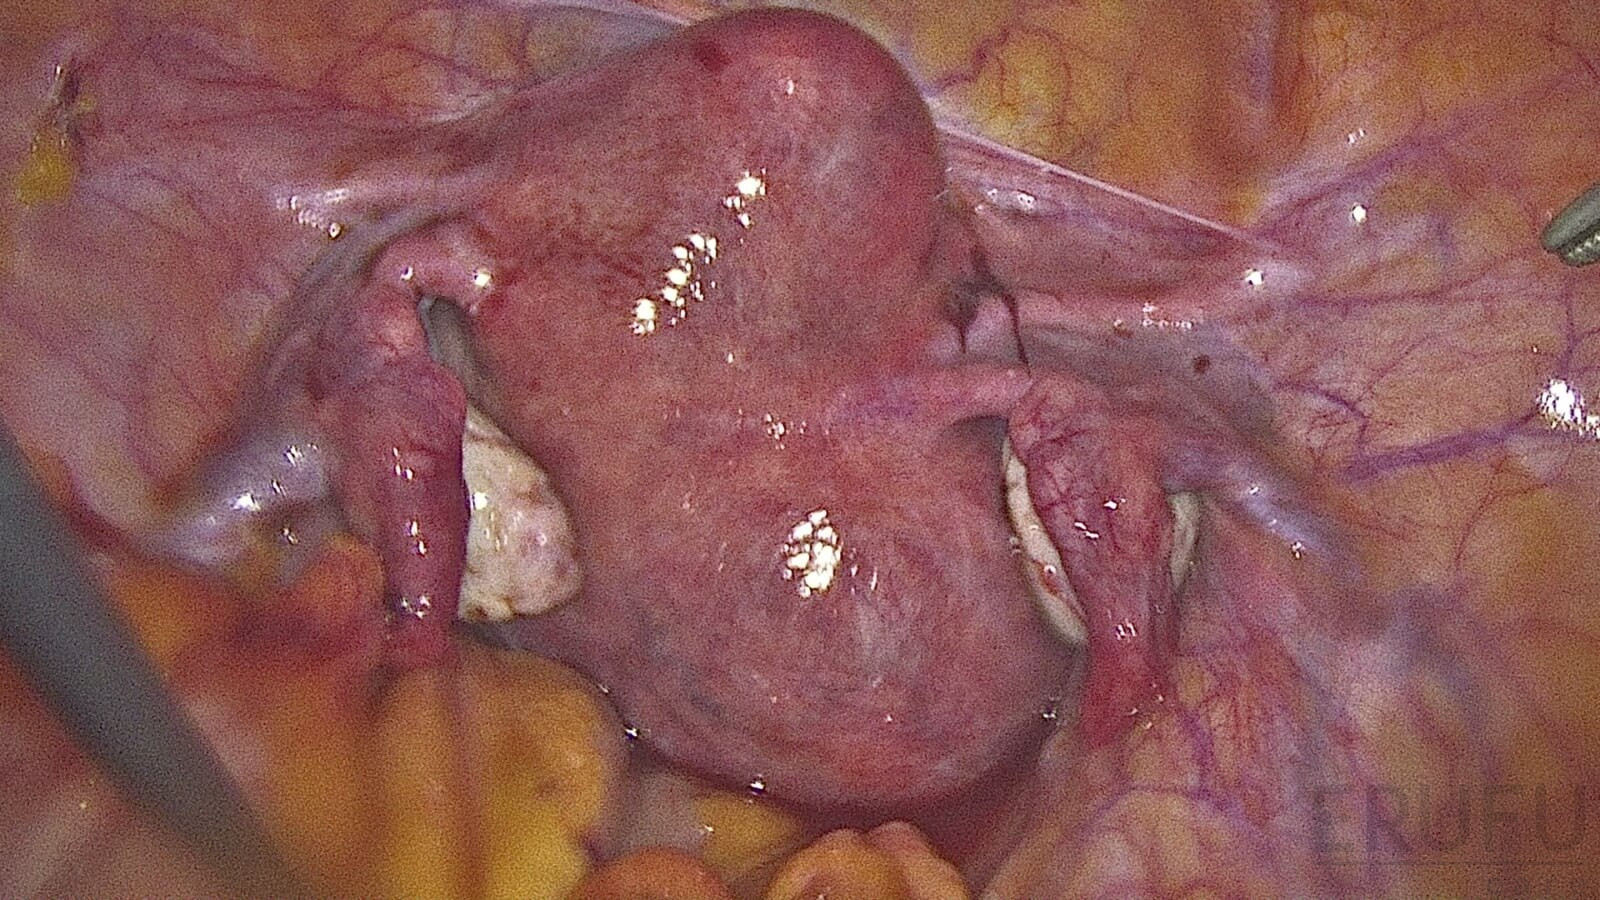

Dysmenorrhea is the pain suffered during menstrual periods, also known as menstrual cramps. While certain degree of period pain is normal, sometimes dysmenorrhea can also be a sign of underlying health conditions like endometriosis. If you consistently suffere from very painful periods, it is best to have a consultation with a women specialist doctor to diagnose any potential health risk.